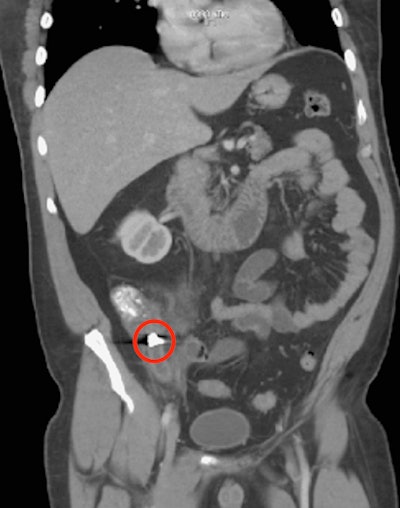

Imaging revealed a 1 x 0.9 cm metallic density in the man's appendix, as well as inflammatory findings consistent with acute appendicitis. Imaging also showed a lack of normal muscle contractions in the intestines in the man's regional right lower quadrant, the authors wrote.

An abdominal x-ray revealed a 1 x 0.9 cm metallic density, which ended up being a dental crown, in the appendix near its origin in the cecum. Images courtesy of Brennan et al. Licensed by CC BY 4.0.

A CT scan also confirmed a metallic object -- a dental crown -- in the patient's appendix.Based on the imaging, clinicians diagnosed the man with acute appendicitis. He was prescribed prophylactic preoperative antibiotics, then underwent a successfully completed robot-assisted appendectomy.